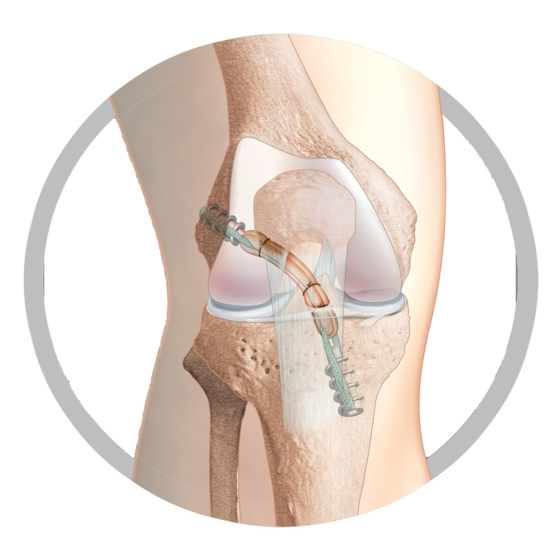

Short Graft ACL

The original short-graft ACL reconstruction technique

Unique to the TLS system is its hand reamed retrograde tunnels which gives the possibility to fine-tune tunnel position per-operatively. As a result, studies have shown the TLS to produce less post-operative pain than traditional techniques and other short graft procedures² whilst also producing excellent long-term patient outcomes.